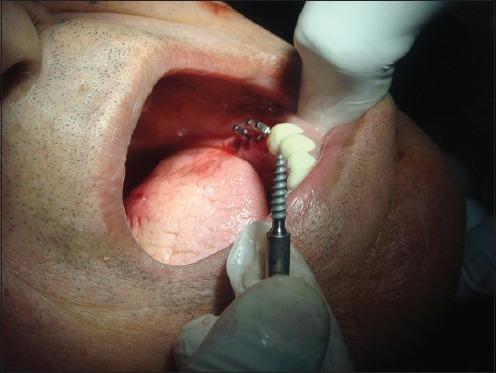

The replacement of missing teeth with implant-borne restorations has become a treatment modality accepted by the scientific community for fully and partially edentulous patients. Recent reports have demonstrated the successful placement of dental implants into the fresh extraction socket in the anterior as well as in molar regions, which is made possible due to modification in implant surface. The present case report highlights the placement of three bicortical screw (BCS) implants into the fresh extraction sockets and one KOS implant in edentulous area with flapless technique. All the implants were immediately loaded and followed up for a period of 6 months.

用种植体支持的修复体替代缺失牙已成为科学界认可的针对全口和部分牙列缺失患者的一种治疗方式。近期报告显示,由于种植体表面的改良,已成功将牙种植体植入前牙区以及磨牙区的新鲜拔牙窝。本病例报告重点介绍了采用不翻瓣技术将3枚双皮质骨螺钉(BCS)种植体植入新鲜拔牙窝以及在无牙区植入1枚KOS种植体的情况。所有种植体均即刻负重,并随访6个月。